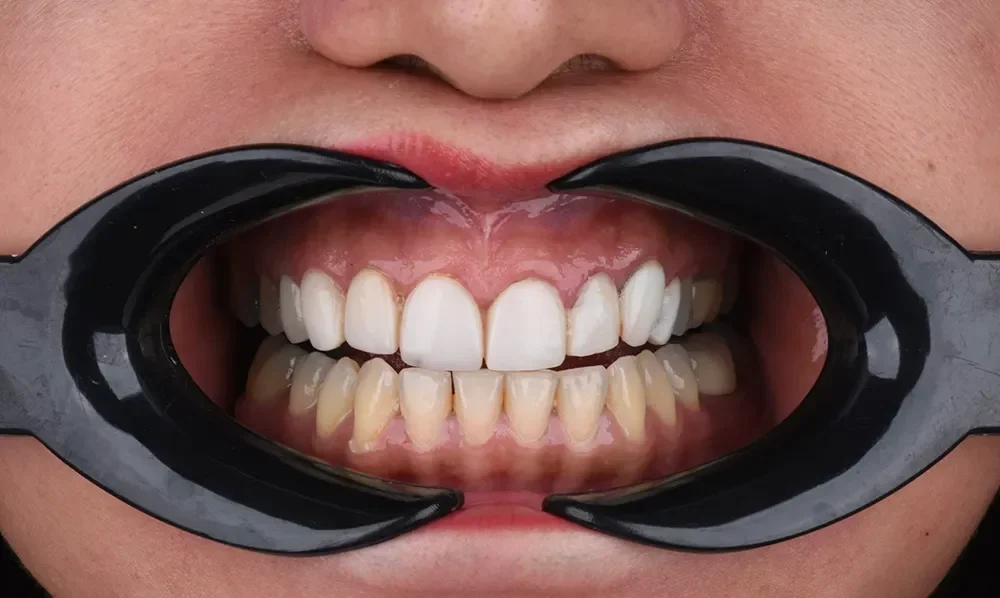

وضعیت اولیه: نارضایتی از کامپوزیتهای قدیمی

تغییر رنگ و کدر شدن کامپوزیتهای قدیمی.

التهاب خفیف لثه ناشی از درمان قبلی.

فرم دندانهایی که حس “مصنوعی بودن” را منتقل میکرد.

۱. حذف کامپوزیت و درمان لثه: در گام نخست، تمامی کامپوزیتهای قدیمی با دقت میکروسکوپی برداشته شدند. اولویت دکتر سمانه علایی قبل از هر کار زیبایی، سلامت بافتهای نگهدارنده است. بنابراین ابتدا التهاب لثه درمان شد تا بستری سالم برای لمینتها فراهم شود.(ونیر کامپوزیت بدون تراش در اصفهان)

۲. آمادهسازی مینیمال (Minimal Prep): خبر خوب برای این بیمار عزیز این بود که به دلیل سابقه تراش در کامپوزیتهای قبلی، نیاز به تراش مجدد دندانها تقریباً صفر بود. تراش دندانها بسیار محدود و محافظهکارانه انجام شد تا مینای دندان حفظ شود.